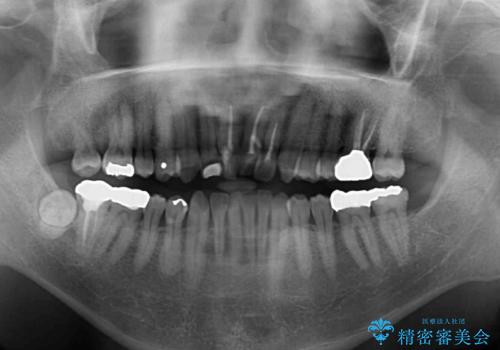

上顎の狭窄歯列 インビザラインによる拡大矯正

- 前歯の叢生と臼歯のクロスバイトを気にして来院された患者様です。

急速拡大装置による上顎の側方拡大を行い、その後はインビザラインより歯列を改善することとしました。

20代後半以降の男性は上顎骨の側方拡大処置の成功率が低く、今回も骨を拡大することができませんでした。

しかしながら、歯列を側方に拡大することができ、その後はインビザラインにて叢生を解消することができました。